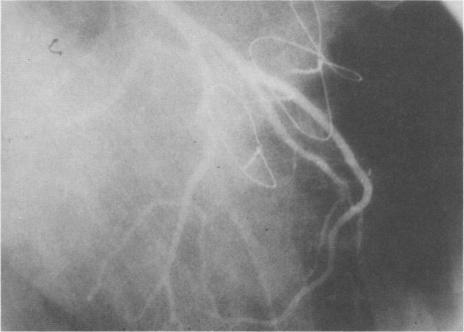

Hypertrophic obstructive cardiomyopathy in combination with anomalous insertion of papillary muscle directly into anterior mitral leaflet and "sawfish" systolic narrowing of the left anterior descending coronary artery.

This report describes an unusual case of subaortic stenosis in which hypertrophic obstructive cardiomyopathy was found in combination with both anomalous insertion of papillary muscle directly into the anterior mitral leaflet and "sawfish" systolic narrowing of the left anterior descending coronary artery. Definitive diagnosis was made on operation. We freed the left anterior descending coronary artery by incising the muscular bridge, resected both papillary muscles, and replaced the mitral valve.